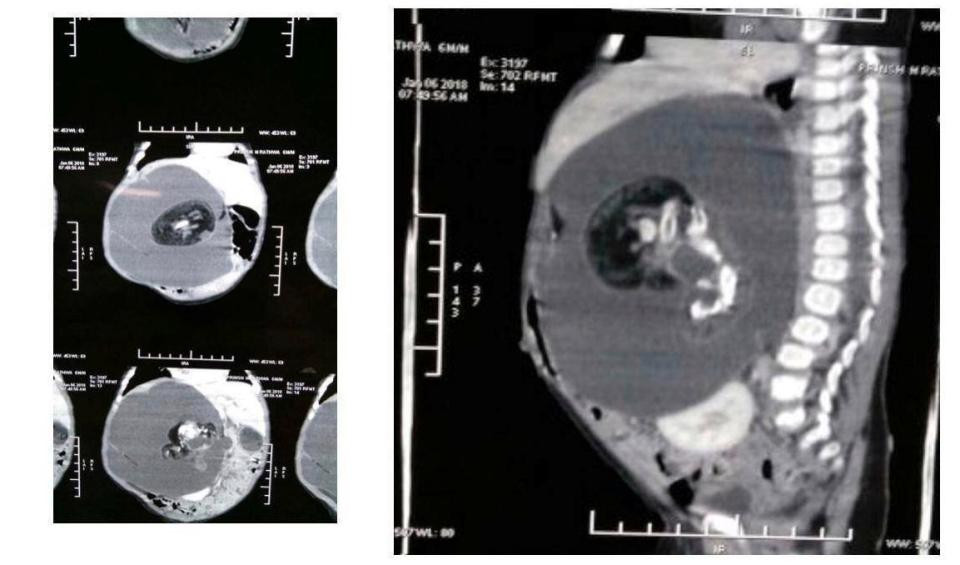

X-quang của Prinsa Rathava cho thấy, bào thai đang phát triển bên trong.

Trưởng phòng phẫu thuật khoa nhi của bệnh viện Nội trú Gujarat, bác sĩ Rakesh Joshi, cho biết: "Bào thai trong bụng của Prinsa nặng 130 g, đã có cột sống, não, đầu, cánh tay và hậu môn. Nó nằm giữa khu vực dạ dày và hai quả thận của Prinsa. Bé gái đang trong tình trạng hồi phục sau khi mổ. Cô bé sẽ sớm xuất viện và nếu không có biến chứng thì cô bé sẽ lớn lên khỏe mạnh, bình thường”.